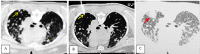

More than 40 different species of the parasitic flatworm Paragonimus have been identified worldwide, including in Vietnam, but only 10 species are known to cause disease in humans, particularly Paragonimus westermani. Paragonimus are transmitted through the ingestion of raw foods, especially freshwater shrimp, and crab. Paragonimiasis causes pneumonia, which can present as acute or chronic, with symptoms including prolonged cough, chest pain, shortness of breath, and hemoptysis. Hematologic changes include eosinophilia and the presence of specific antibodies for Paragonimus in the blood. Diagnosis is confirmed when Paragonimus specimens or eggs are found in the sputum or pleural fluid. The specificity of imaging is not high, but imaging can be used to guide the diagnosis. After the failure of microbiological diagnostic methods, lung biopsy can be used to confirm a diagnosis of paragonimiasis. We present a paragonimiasis case associated with unique features, including epidemiologic factors, atypical clinical signs, no increases in blood eosinophils, and negative microbiological tests. Although the patient was suspected of tuberculosis or lung cancer, imaging studies were consistent with the presence of lung flukes. Three transthoracic lung biopsies were performed, and pathology revealed a cystic structure containing Paragonimus on the third biopsy.